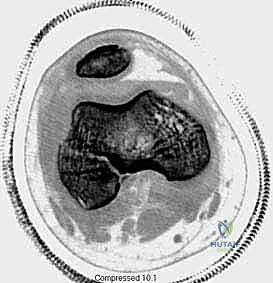

3. التصوير المقطعي المحوسب (CT Scan)

يطلبه الدكتور محمد هطيف في حالات الكسور المعقدة التي تمتد إلى داخل سطح المفصل (Intra-articular fractures). يساعد التصوير المقطعي ثلاثي الأبعاد في التخطيط الجراحي الدقيق لضمان إعادة السطح المفصلي إلى نعومته الطبيعية لمنع خشونة الركبة المبكرة.

4. استخدام تقنيات المناظير (Arthroscopy 4K)

في الكسور التي تمتد لداخل المفصل (النوع الثالث والرابع)، قد يستخدم الدكتور هطيف منظار الركبة بدقة 4K لرؤية السطح المفصلي من الداخل والتأكد من تطابقه بنسبة 100%، وإزالة أي شظايا غضروفية حرة قد تعيق حركة الركبة مستقبلاً.